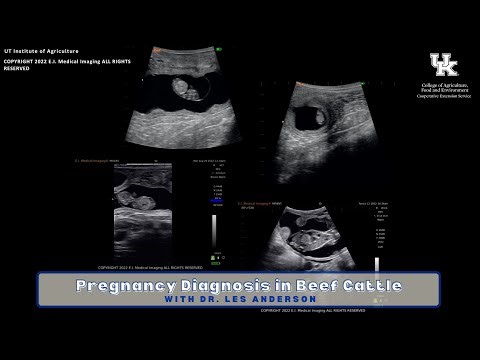

Pregnancy Diagnosis in Beef Cattle

已浏览 380 次

3 个月之前

YouTube

Warren County Agriculture